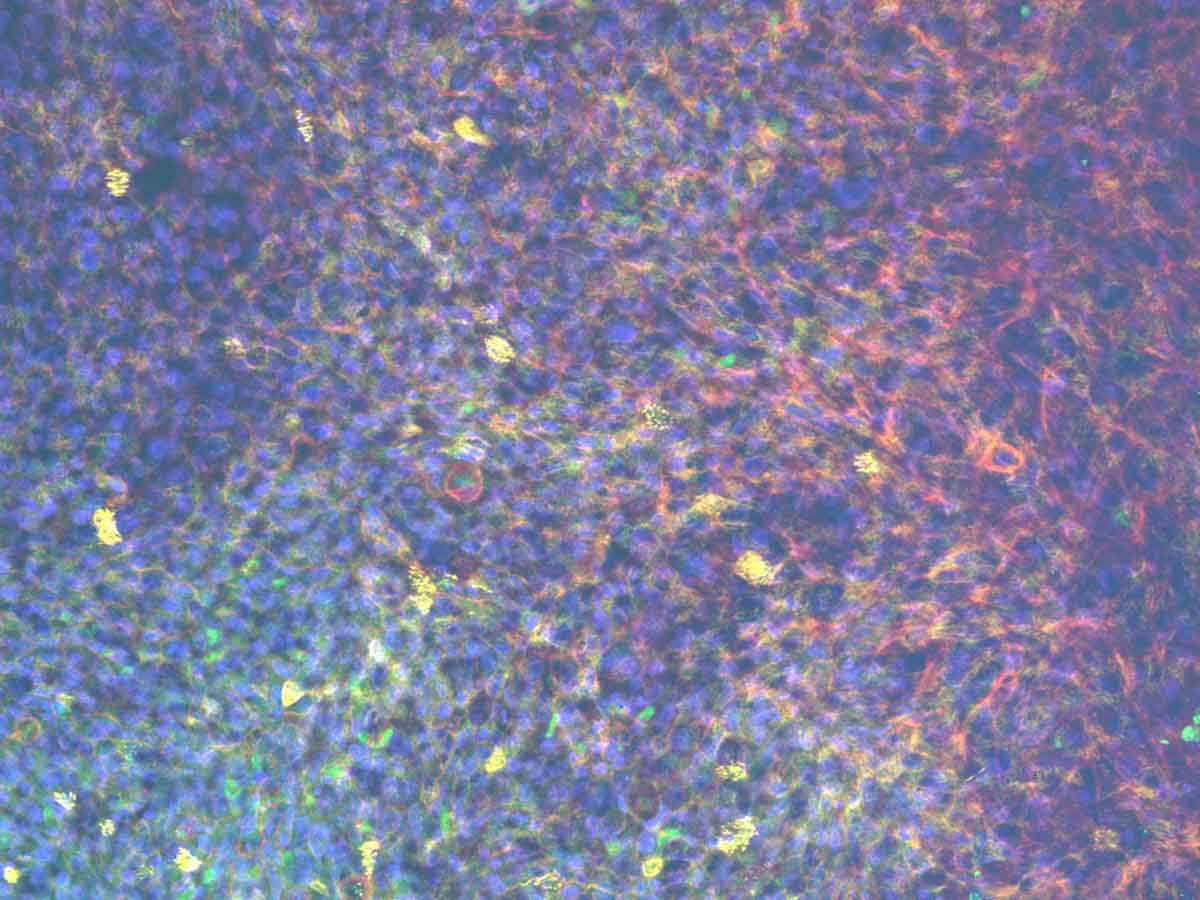

Primary human bronchial epithelial and endothelial cells are cultured on either side of an insert scaffold at air-liquid-interphase (ALI) to produce a pseudostratified epithelium over 14 days.

Culturing in perfusion enhances the differentiation of the bronchial epithelium with a functional mucociliary barrier retained for long-term culture.

Have you characterized single cell transcriptomics of the lung-on-a-chip model?.

No, we have not undertaken single cell transcriptomics in the lung models – but it’s something we would like to do in the future to get a full picture of the model and how it compares to the human lung. We have performed qPCR analysis to demonstrate the presence of cell markers of key cell types (AT I / II markers in the alveolar model. Goblet, Club cell and ciliated epithelium markers in the bronchial model). This analysis showed an upregulation of these cell markers in the tissues cultured by the PhysioMimix OOC System. Large differences in gene expression have also been quantified using microscopy. When we add further complexity to the model (e.g., via the incorporation of endothelial cells), we observe further upregulation of these cell markers, which is indicative of enhanced cell-cell communication and a more physiologically relevant phenotype.

We also focus on the cell phenotypes formed after differentiation at air-liquid interface (ALI), particularly the alveolar and bronchial epithelial cell phenotypes, to ensure they are forming lung tissues that resemble the human lung. For example, when thinking about the alveolar model we ensure that the cell population remains at a good ratio of alveolar epithelial type I (ATI) to alveolar epithelial type 2 (ATII) cells. In other model systems this balance is often skewed towards an ATI alone population which is not representative of in vivo alveoli.